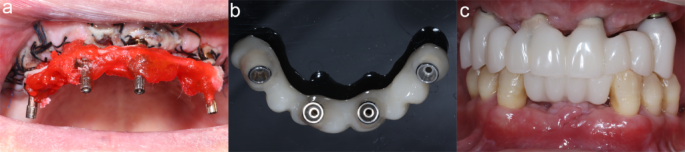

Immediate restoration. a, Impression with splint. b, Immediate prosthesis. c, Completion of immediate restoration.

An immediate impression was obtained using a stabilization splint, and the occlusal relationship following surgery was recorded (Fig. 3a). Subsequently, computer-aided design/computer-aided manufacturing (CAD/CAM) resin prostheses were fabricated (Fig. 3b). The prosthetic length was determined based on the distal implant location to prevent cantilever and restore 6 to 8 teeth. The immediate restoration was completed within one week postoperatively (Fig. 3c). To ensure proper placement of the prosthesis, panoramic imaging was performed (Fig. 4). Patients were advised to consume soft foods and utilize an irrigator and interproximal brushes to maintain oral hygiene.

Panoramic imaging of immediate restoration.